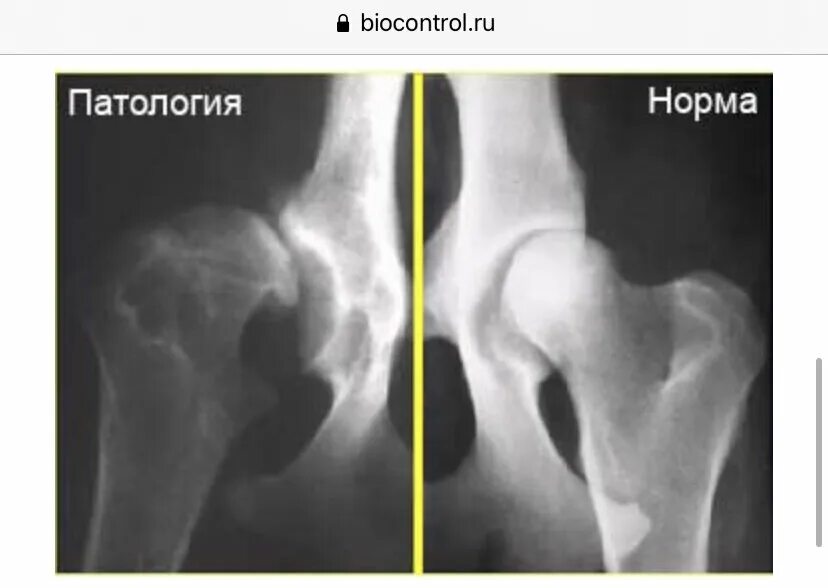

Дисплазия тазобедренных суставов как выглядит